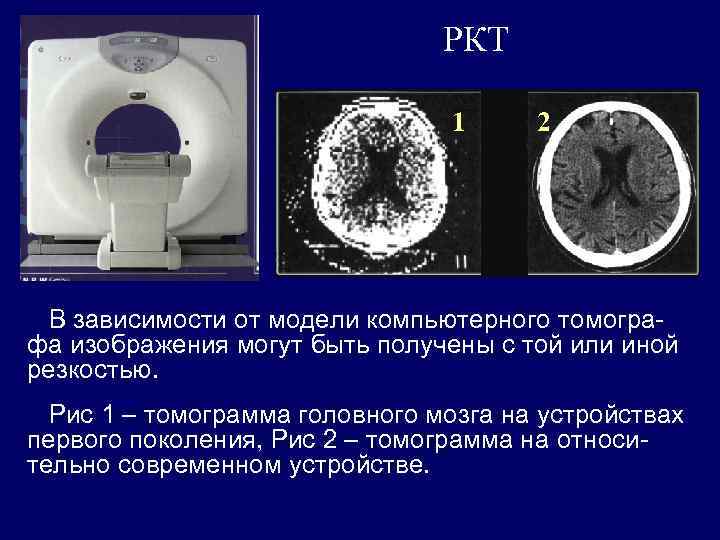

РКТ 1 2 В зависимости от модели компьютерного томографа изображения могут быть получены с той или иной резкостью. Рис 1 – томограмма головного мозга на устройствах первого поколения, Рис 2 – томограмма на относительно современном устройстве.